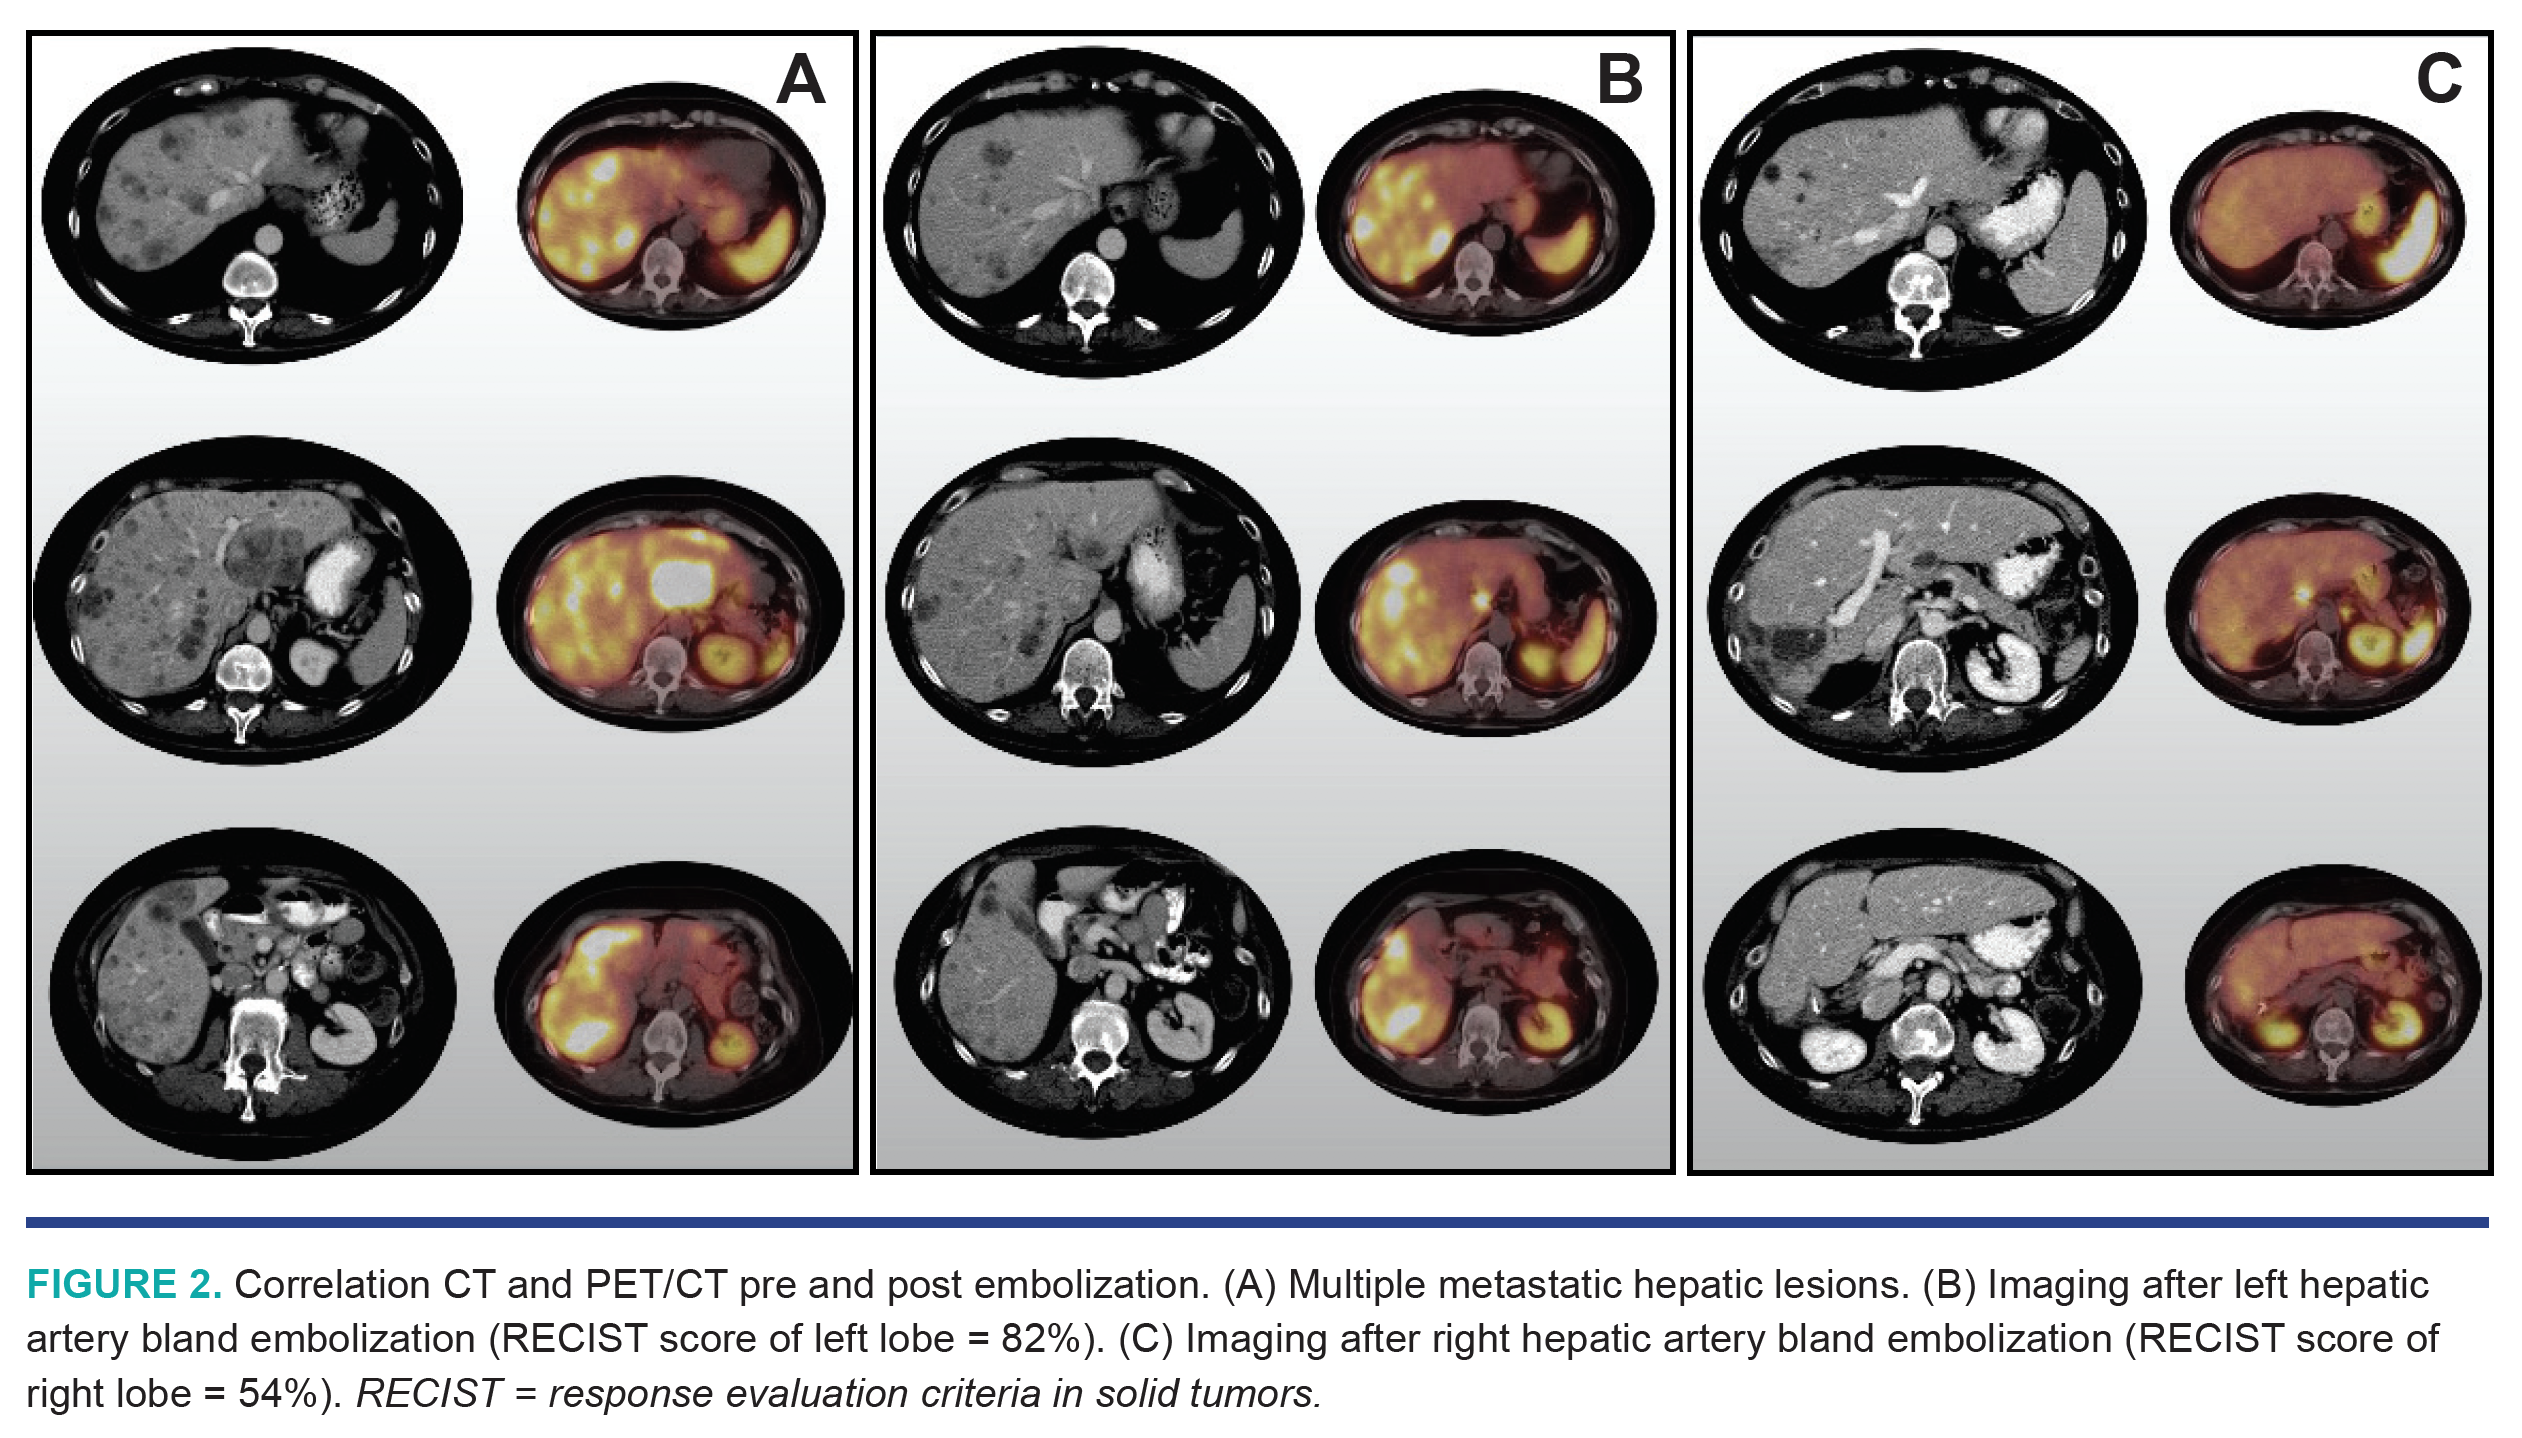

A 63-year-old woman presented with diarrhea and unintentional weight loss. Positron emission tomography (PET) and computed tomography (CT) of the abdomen and pelvis showed multiple hepatic metastatic lesions and a soft tissue mass along the terminal ileum. Liver biopsy confirmed a low-grade neuroendocrine tumor (antigen Ki-67, 1.9%). She was initiated on octreotide and everolimus. A few months later, a PET-CT scan with Gallium-68 dotatate radiotracer demonstrated a somatostatin-analog avid nodule projecting to the terminal ileum and multifocal sites of intense somatostatin-analog localization within both lobes of the liver consistent with hepatic metastases (Figures 1A and 2A; Video 1). Due to the patient’s progressive disease, she underwent bland hepatic embolization (Figure 1B) of the left lobe (Figure 2B; Video 2) using 250 micron Embozene microspheres (Varian Medical Systems) followed by right hepatic lobe bland embolization (Figure 2C; Video 3) using 250 micron Embozene microspheres a few months later. She then underwent resection of the primary site at the terminal ileum, and is now clinically asymptomatic.